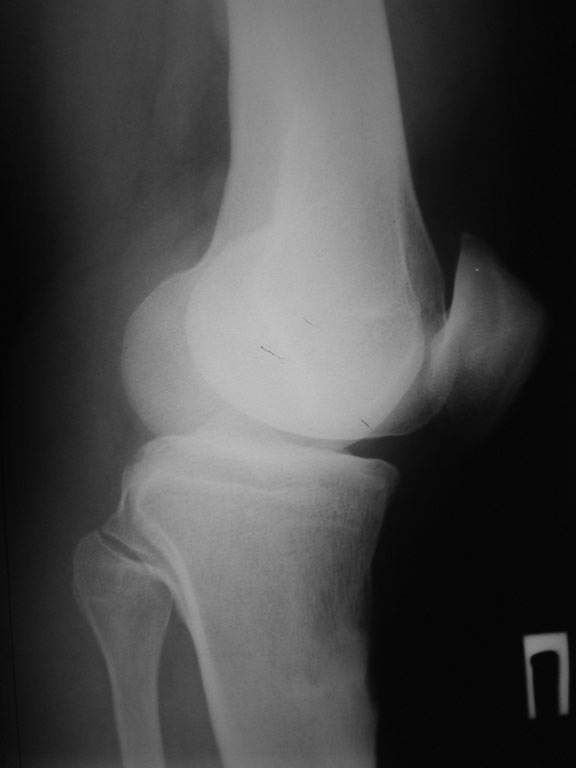

пациент наконец то объявился вновь и мы смогли выполнить новые снимки как лежа так и в нагрузке

если у вас остались силы, давайте обсудим

Уважаемый доктор Зайцев! Причина деформации проксимальной тибии у Вашего пациента - преждевременное и несимметричное закрытие зоны роста передней части проксимальной ростковой зоны б/б кости в следствии окультной травмы произошедшей в возрате 10-12 лет. Есть 2 причины рекурвационной деформации в области коленного сустава - мягкотканевая и костная.В данном случае Вы имеете дело не с рукурвацией коленного сустава, а с рекурвационной деформацией проксимальной голени. "Заднего выдвижного положения" на самом деле нет.То, что Вы видите на боковом снимке - это не задний подвывих голени - это снимок, сделанный в сгибании коленного сустава. Дело в том, что костные дефорсации в области коленного хорошо компенсируются за счёт движения в суставе. поэтому то, что вы видите, как задний подвывих на самом деле - сгибательное положение колена.

Соответственно, для планирования коррекции необходимы сравнительные функциональные рентгенограммы, т.е. профиль в максимальном разгибании коленных суставов.

Если суставная площадка tibia занимает при "переразгибании" колена то же положение, что будет видно на здоровом суставе, то при коррекции формы tibia компенсаторная сгибательная установка коленного сустава самоликвидируется. Опора на бедро и прочее будет избыточно. По-моему, там именно такая ситуация.